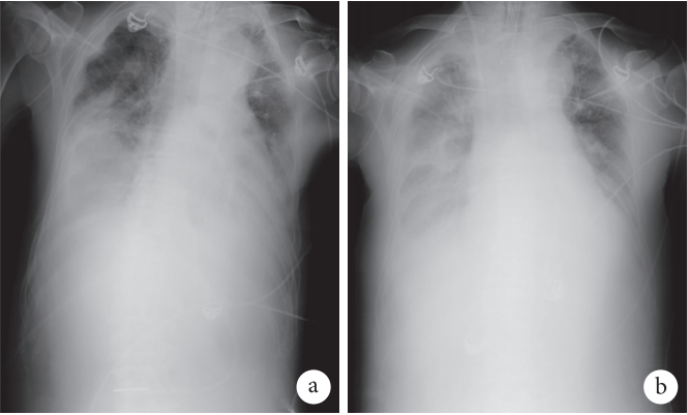

10月4日患者体温再次升高至37.5℃,复查血常规提示WBC 29.36×109/L,NEU% 97.0%,PLT 151×109/L;感染指标:CRP 366.3 mg/L,IL-6>1521.0 pg/ml,PCT 20.8 ng/ml。复查胸部X线片较9月29日明显进展(图2)。考虑不除外呼吸机相关性肺炎(VAP),调整抗生素为头孢哌酮舒巴坦+替加环素+环丙沙星+阿奇霉素,并再次复查气管镜,行BAL送检细菌培养及mNGS。

图2  患者2019年9月29日及10月10日胸部X线检查像

注:a. 双肺多发斑片影,双下肺为著;b. 双肺斑片影进展,尤其右肺透亮度显著下降。